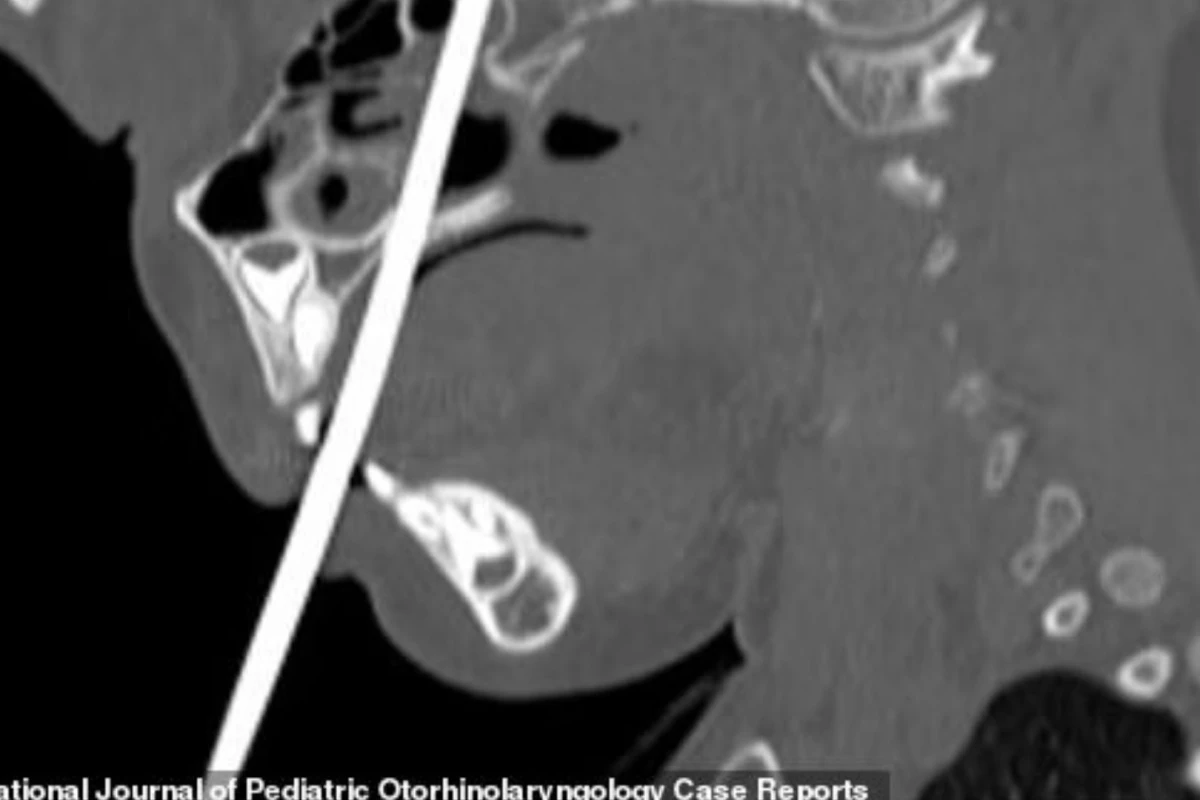

A menina pulava em cima da cama com o objeto quando teve o céu da boca perfurado.